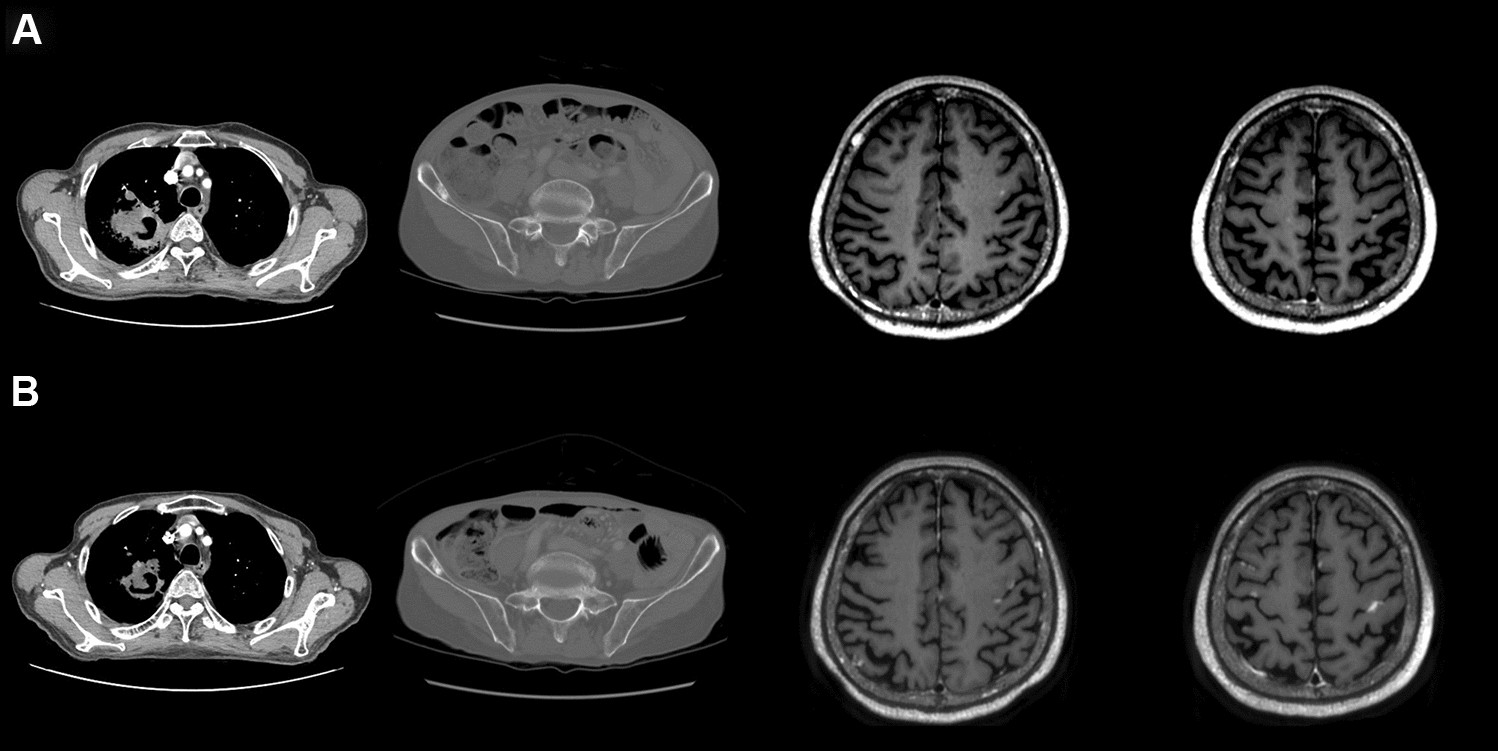

Figure 3

A typical case with brain metastases that showed disease progression after receiving only chemotherapy without whole-brain radiotherapy. Compared to the time of lung cancer diagnosis (A), the size of the primary tumor decreased and that of the metastatic lesion in the right iliac bone did not change after two cycles of platinum-based chemotherapy (B). However, the size of metastatic lesions in the brain increased and new metastatic lesions developed.